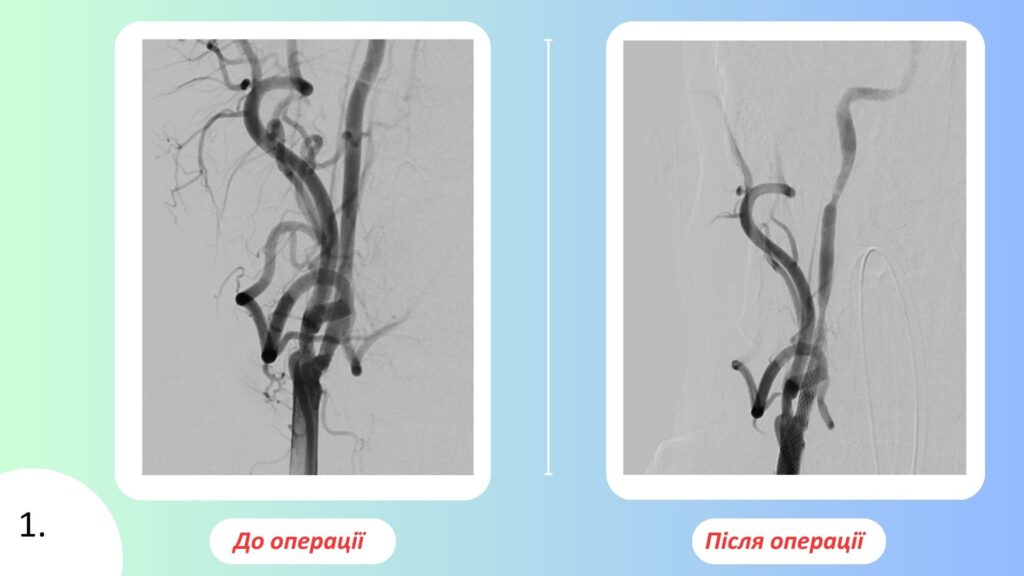

Перший клінічний випадок стосувався військовослужбовця, який перебуває на службі з 2015 року та мав тривалу цереброваскулярну патологію. На тлі атеросклеротичного ураження магістральних артерій голови у пацієнта сформувався симптомний тандемний стеноз правої внутрішньої сонної артерії, що клінічно проявлявся частими транзиторними ішемічними атаками. Після комплексного обстеження та церебральної ангіографії було ухвалено рішення про невідкладне ендоваскулярне втручання. Пацієнту виконано транслюмінальну ангіопластику зі стентуванням уражених сегментів, досягнуто повну стабілізацію кровотоку, післяопераційний період минув без ускладнень, що дало змогу продовжити підготовку до подальшого кардіохірургічного лікування.